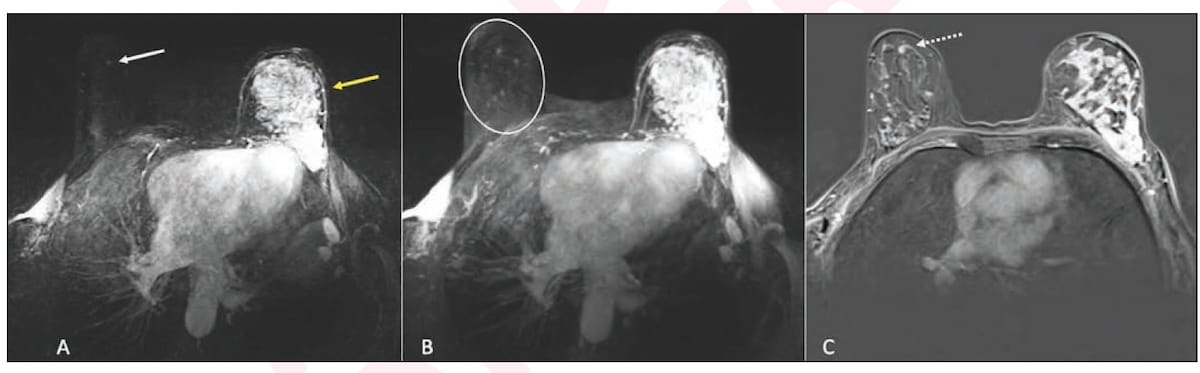

Here one can see the use of ultrafast magnetic resonance imaging (MRI) and post-contrast subtraction MRI in staging for a 63-year-old woman who had multicentric mixed ductal and lobular invasive cancer in the left breast. The imaging revealed an 0.4 cm focus in the right breast that was subsequently diagnosed with MRI-guided biopsy as a ductal carcinoma in situ (DCIS). (Images courtesy of the American Journal of Roentgenology.)